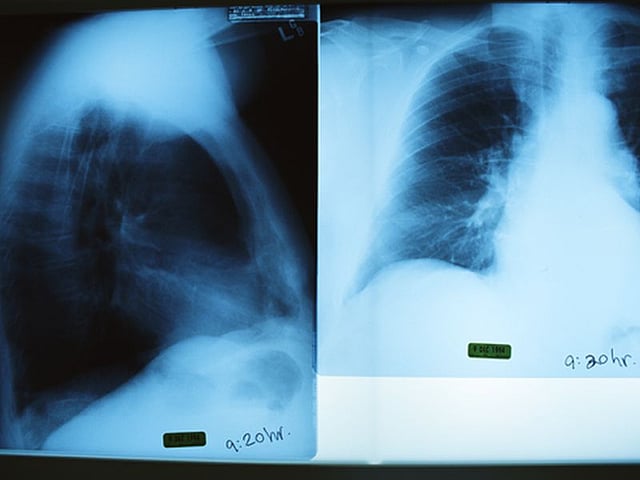

An X-ray is an imaging test that a medical professional can use to diagnose a condition or an injury. In fact if you really. An urgent chest X-ray should be offered to be performed within 2 weeks to assess for lung cancer in people aged 40 and over if they have 2 or more of the following unexplained.

Chest X Ray Purpose Procedure And Risks